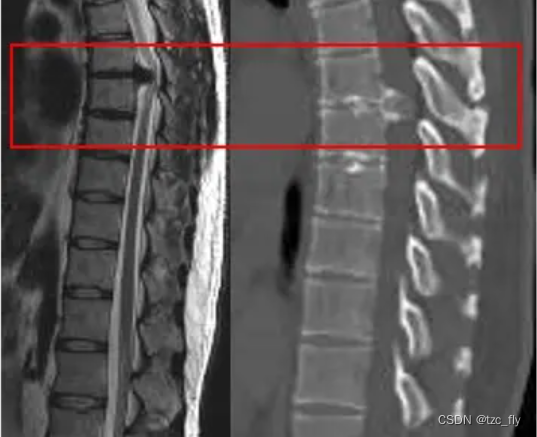

- 患者的MRI(左)看到椎体后方突出物进入椎管,容易被诊断为是一个椎间盘突出,完善CT(右)检查发现是一个密度不均匀的占位病变,原来是在T6/7平面的椎间隙后缘长了肿瘤(骨软骨瘤)。